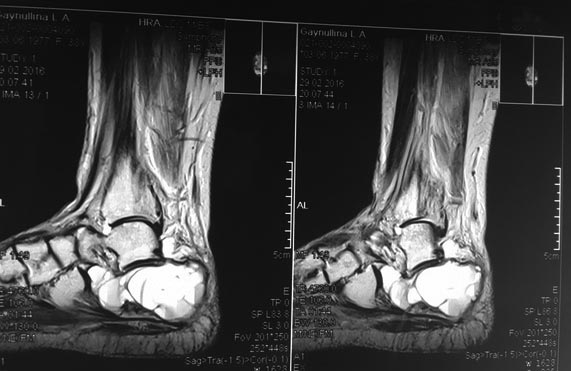

Пациентка Г., 38 лет. 1,5 года назад появились боли в левой пяточной кости.

Болей в покое и ночных болей нет. 08.09.15 операция: экскохлаеция аневризмальной костной кисты, пластика деминерализованными костными трансплантатами. По данным МРТ (29.02.16) костной перестройки нет, вероятно произошел выход содержимого кисты в пространство позади ахиллова сухожилия. Планируется проведение РКТ, биопсии. Вопрос: чем можно заполнить ? Костный цемент? Или снова деминерализованные костные трансплантаты?